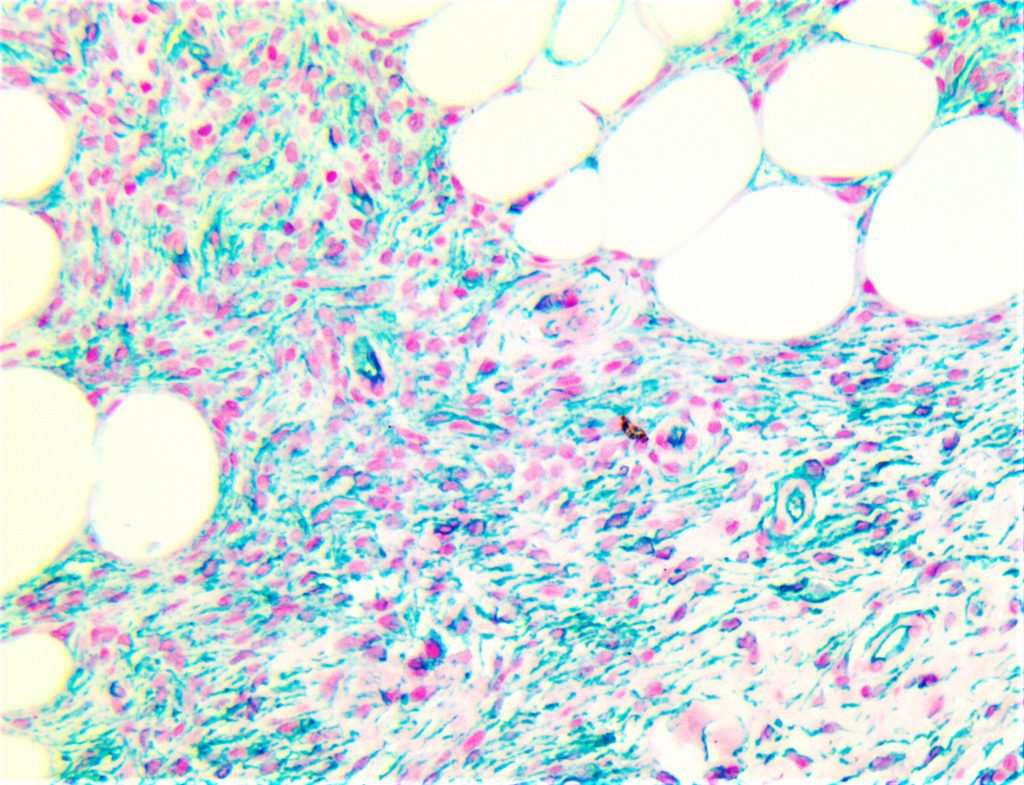

Bio SB has developed high affinity IVD monoclonal antibodies for fast immunohistochemistry (IHC) detection of melanoma, basal cell carcinoma (BCC), squamous cell carcinoma (SCC) and other Mohs surgery related conditions. Combined with our innovative IHC detection systems, we are opening the doors to a faster and more accurate immunohistochemistry applicable to Mohs surgery.

Bio SB has developed a fast, non-biotin monovalent Fab micropolymer IHC detection system for the detection of IVD antibodies for melanoma, BCC, SCC and other Mohs surgery related conditions. Our innovative IHC detection systems have opened the doors for a faster and accurate immunohistochemistry applicable to Mohs surgery.